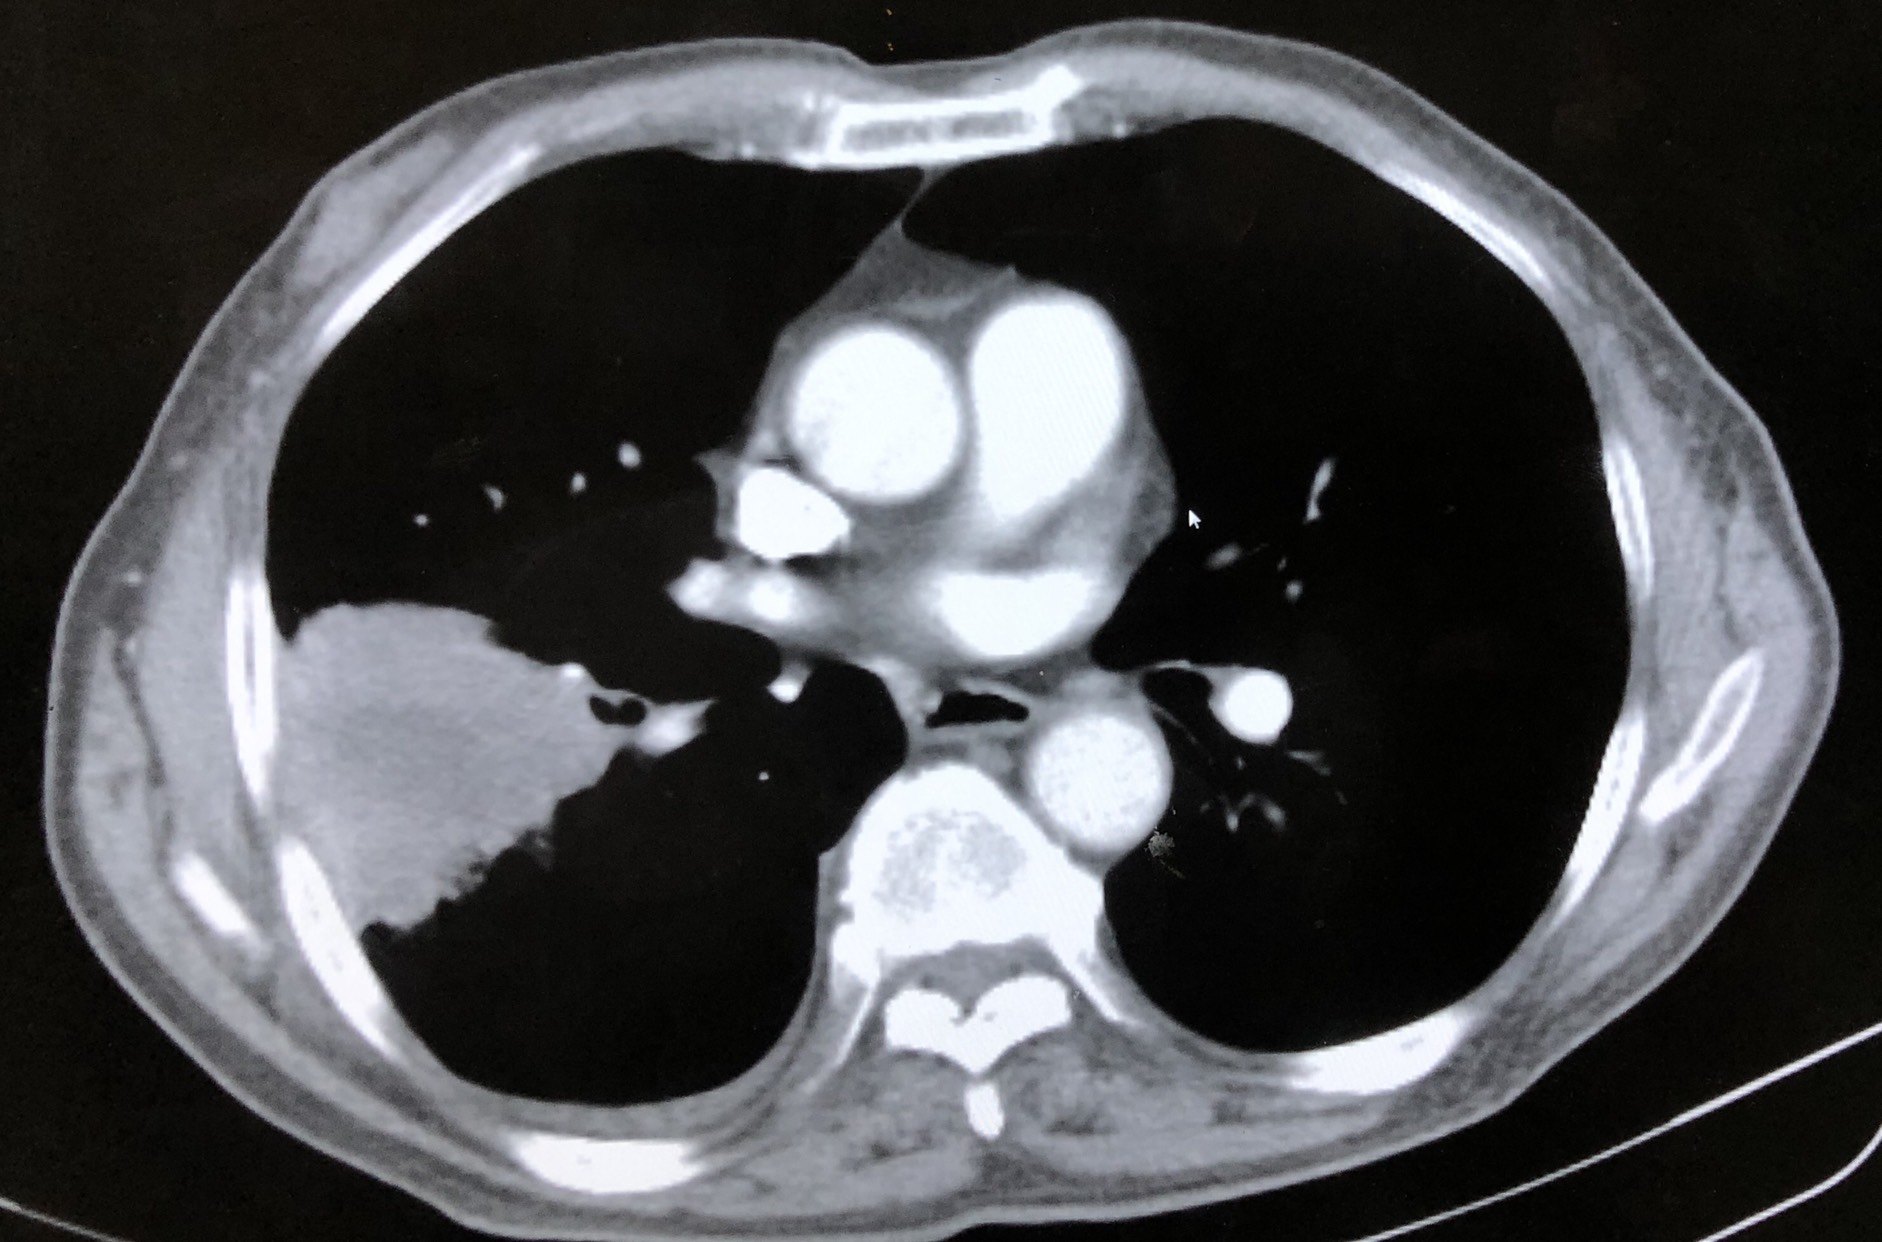

图1 右肺占位